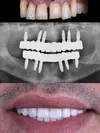

Implant Treatment